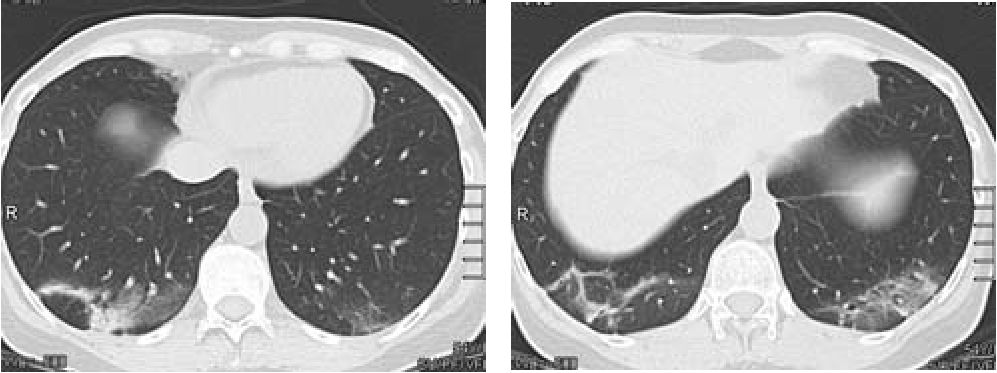

Спустя 2 нед. от начала лечения наблюдалась дальнейшая положительная динамика: отсутствие жалоб, уменьшение СОЭ до 42 мм/ч, при контрольной КТ грудной клетки - уменьшение размеров и плотности инфильтратов в легких (рис. 6).

Рис 6. Рентгеновская компьютерная томография 29:07.10 Аксиальная проекция.

Через 2 недели стероидной терапии выраженная положительная динамика в виде значительного уменьшения выраженности, размеров и интенсивности выявляемых ранее изменений.

Еще через 2 мес. инфильтрация в ткани легких уже не определялась (рис. 7), СОЭ - 30 мм/ч, СРБ - 4 мг/л.

Рис. 7. Рентгеновская компьютерная томография 08.10.10 Аксиальная проекция.

Через 2 месяца полный регресс ранее выявляемых изменений.